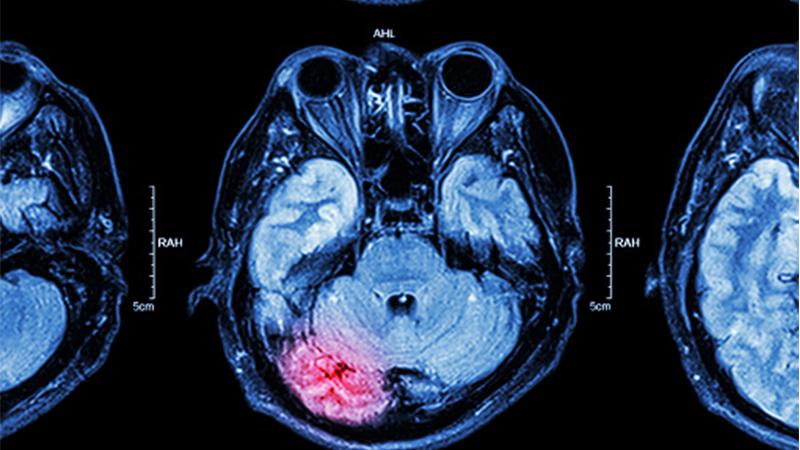

A Model Way to Detect Delayed Cerebral Ischemia

Neurologists and neurosurgeons at NewYork-Presbyterian/Columbia University Irving Medical Center have developed a classification model to alert clinicians to delayed cerebral ischemia (DCI), helping to provide an opportunity to reduce neurological injury following an aneurysmal subarachnoid hemorrhage. As there are no existing monitors for DCI, the Columbia team sought to identify an alternative approach to diagnosis by applying machine learning models for DCI classification that would involve the development of hourly risk scores. The model was based on vital sign measurements and demographics routinely collected for clinical care cross-referenced with 22 time-varying physiological measures. Computation of data from patients with subarachnoid hemorrhage included mean, standard deviation, and cross-correlation of heart rate time series with each of the other vitals to explore optimal machine learning models for DCI classification. This is the first study to show that real-time hourly risk scores can classify DCI with good accuracy following an aneurysmal subarachnoid hemorrhage and that an automated, continuous monitoring tool has the potential to provide ongoing real-time risk assessment for DCI that can be implemented in any ICU.

Up to every third patient with an aneurysmal subarachnoid hemorrhage will present with delayed cerebral ischemia that can lead to devastating functional and cognitive consequences.